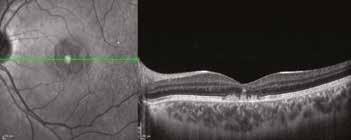

Il DHA costituisce infatti più del 30% dei lipidi strutturali dei neuroni e fino al 60% di quelle della neuro-retina esterna. In particolare, la biodisponibilità dell’olio algale OMEGAL DHA è di gran lunga maggiore, rispetto al DHA da pesce, se si prende in considerazione una integrazione spesso necessaria. Il miglioramento della fluidità di membrana a livello degli strati neuro-retinici esterni permette un miglior scambio metabolico a livello dell’interfaccia epitelio pigmentato retinico (EPR)-corio-capillare e una migliore funzionalità delle cellule foto-recettoriali foveali, anche per un miglioramento del microcircolo corio-capillare-retinico maculare, migliorando la funzionalità delle membrane endoteliali. In particolare, il DHA interviene nell’adattamento della funzione visiva, durante i periodi di transizione luce-buio nella visione notturna. La mia personale esperienza con la terapia a base di DHA algale (OMEGAL DHA), associato o meno a un integratore a formula Areds2 e/o curcumina, nella cura delle degenerazioni maculari correlata all’età senile (DMS), inizia con alcuni casi clinici osservati negli anni 2009-2010, poi riportati come “Case Reports” al convegno internazionale Retina in progress nel 2011 a Milano che mostrava, come nel caso riportato sotto, un miglioramento, rapido e progressivo, ovviamente insolito, date le caratteristiche degenerative della DMS, degli accumuli lipofuscinici drusenoidi maculari, senza sviluppo di significative aree atrofiche a carico dell’EPR maculare. L’utilizzo integrativo concomitante di altre molecole antiossidanti quali curcumina, astaxan-

tina, acido lipoico e resveratrolo può aiutare a prevenire i danni foto-ossidativi e infiammatori a cui la retina è facilmente esposta, oltre che a stabilizzare il DHA algale nella sua integrazione a tutto spessore nella membrana cellulare e proteggerlo, sia in ambiente lipofilo che idrofilo, impedendo tra l’atro una eccessiva fluidità di membrana che oltre un determinato livello diventa controproducente. (Fig. 1)

12 MESI DHA ALGALE (OMEGAL DHA) Visus 9-10/10;0.04 logm.+0.75 sf

Fig. 1. Imaging infrarosso ed OCT mostra un Rapido ed insolito appianamento di ampio distacco dell’EPR maculare in DMS in donna di 75 aa, con significativo miglioramento visivo da 0.6 logmar a 0.1 logmar e nell’integrità delle linee recettoriale nella zona ellissoide, in particolare in assenza di aree atrofiche successive al riassorbimento.